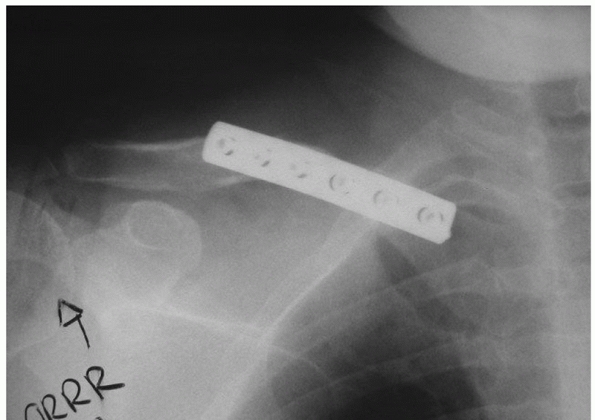

clavicle and planned operative site is important. As with midshaft

in the distal fragment and resisting the primary displacing forces,

scapula) inferiorly.4,22,39,71,75,116

acromion. In this instance, theuse of a hook plate (a precontoured

plate with a projection or “hook” that is inserted posteriorly in the

subacromial space) can be extremely useful, especially with very distal

fractures.48,52,182

screws.49,52,182 This may be readily apparent during preoperative planning (Fig. 36-28)

or may only be realized intraoperatively. The advantage of subacromial

![]()  |

FIGURE 36-28 A.

Anteroposterior radiograph of a very distal clavicle fracture in a 22-year-old female pedestrian struck by a street car. The fracture was open with significant soft tissue damage, near transection of the superior deltoid and trapezius, and severe instability of the shoulder girdle. It can be anticipated that conventional plating may be inadequate given the small size of the distal fragment and the associated shoulder girdle instability. B. Radiograph following irrigation and débridement, hook plate fixation, and deltoid/ trapezial muscle repair. Early motion was initiated and an excellent result ensued.  |